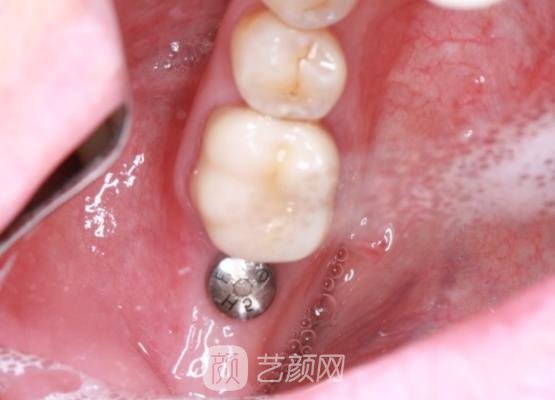

在确认我的身体没有一些特殊情况下,就按照我的牙齿大小和牙齿情况帮我制定了适合我的手术方案供我选择,确定完手术方案后,医生就帮我进行了手术。

手术刚开始时,我也是比较紧张的,一直都在发抖,幸亏医生一直在旁边不断的安慰我,我紧张的情绪才缓解了很多,短短几个小时以后,手术就结束了,并没有浪费我很多的时间,这是我没有想到的。

手术刚结束时,我的牙龈处还有一些红肿的情况,而且还很疼,医生告诉我不用太过于担心,这些现象是比较正常的,然后对我的口腔情况进行了的检查,给我开了一些消炎药,让我定时服用,吃了消炎药以后,我的口腔情况果然缓解了很多。

几个月以后,我的牙齿已经恢复好了,而且成果也是很自然的,口腔也没有一些异常的状况,果然医生的医美技术是比较厉害的,手术成果真的让我很满意,以后身边如果有朋友需要做种植牙手术,我也一定会推荐这家医院的。